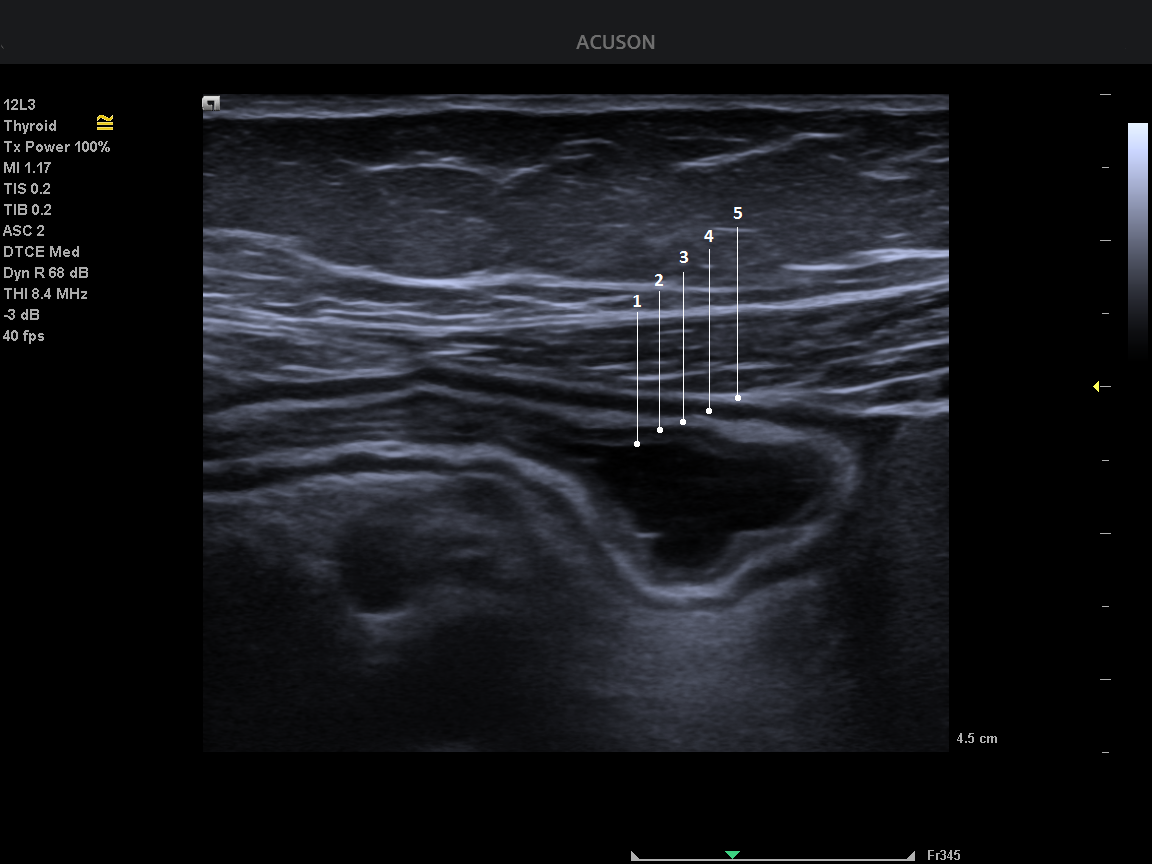

(Ch:29) Ultrasound of tropical (parasitic) diseasesNovember 25, 2020(Ch:28) Classification and US Management of Muscle Injuries in SportNovember 27, 2020 Student Image Challenge 75 Student Image Challenge #75 1 / 1 Student Image Challenge #75 The 5 layers of a normal bowel wall on US imaging are… ? 1 – mucosal interface with lumen (hyperechoic), 2 – mucosa (hypoechoic), 3 – submucosa (hyperechoic), 4 – serosa (hyperechoic), 5 – muscularis (hypoechoic) 1 – mucosal interface with lumen (hyperechoic), 2 – mucosa (hypoechoic), 3 – submucosa (hyperechoic), 4 – muscularis (hypoechoic), 5 – serosa (hyperechoic) 1 – mucosa (hyperechoic), 2- muscularis propria (hypoechoic), 3 – submucosa (hypoechoic), 4 – muscularis (hyperechoic), 5 – serosa (hypoechoic) 1 – mucosal (hyperechoic), 2 – submucosa (hypoechoic), 3 – muscularis (hyperechoic), 4 – serosa (hyperechoic), 5 – subserosa (hypoechoic) Incorrect ....Please see the correct answer highlighted Correct! 1 – mucosal interface with lumen (hyperechoic) 2 – mucosa (hypoechoic) 3 – submucosa (hyperechoic) 4 – muscularis (hypoechoic) 5 – serosa (hyperechoic) Your score isThe average score is 50% LinkedIn Facebook VKontakte 0% Restart quiz Case courtesy of Prof Adrian Saftoiu EFSUMBAdmin Related postsStudent Image Challenge 107Read more Comments are closed.